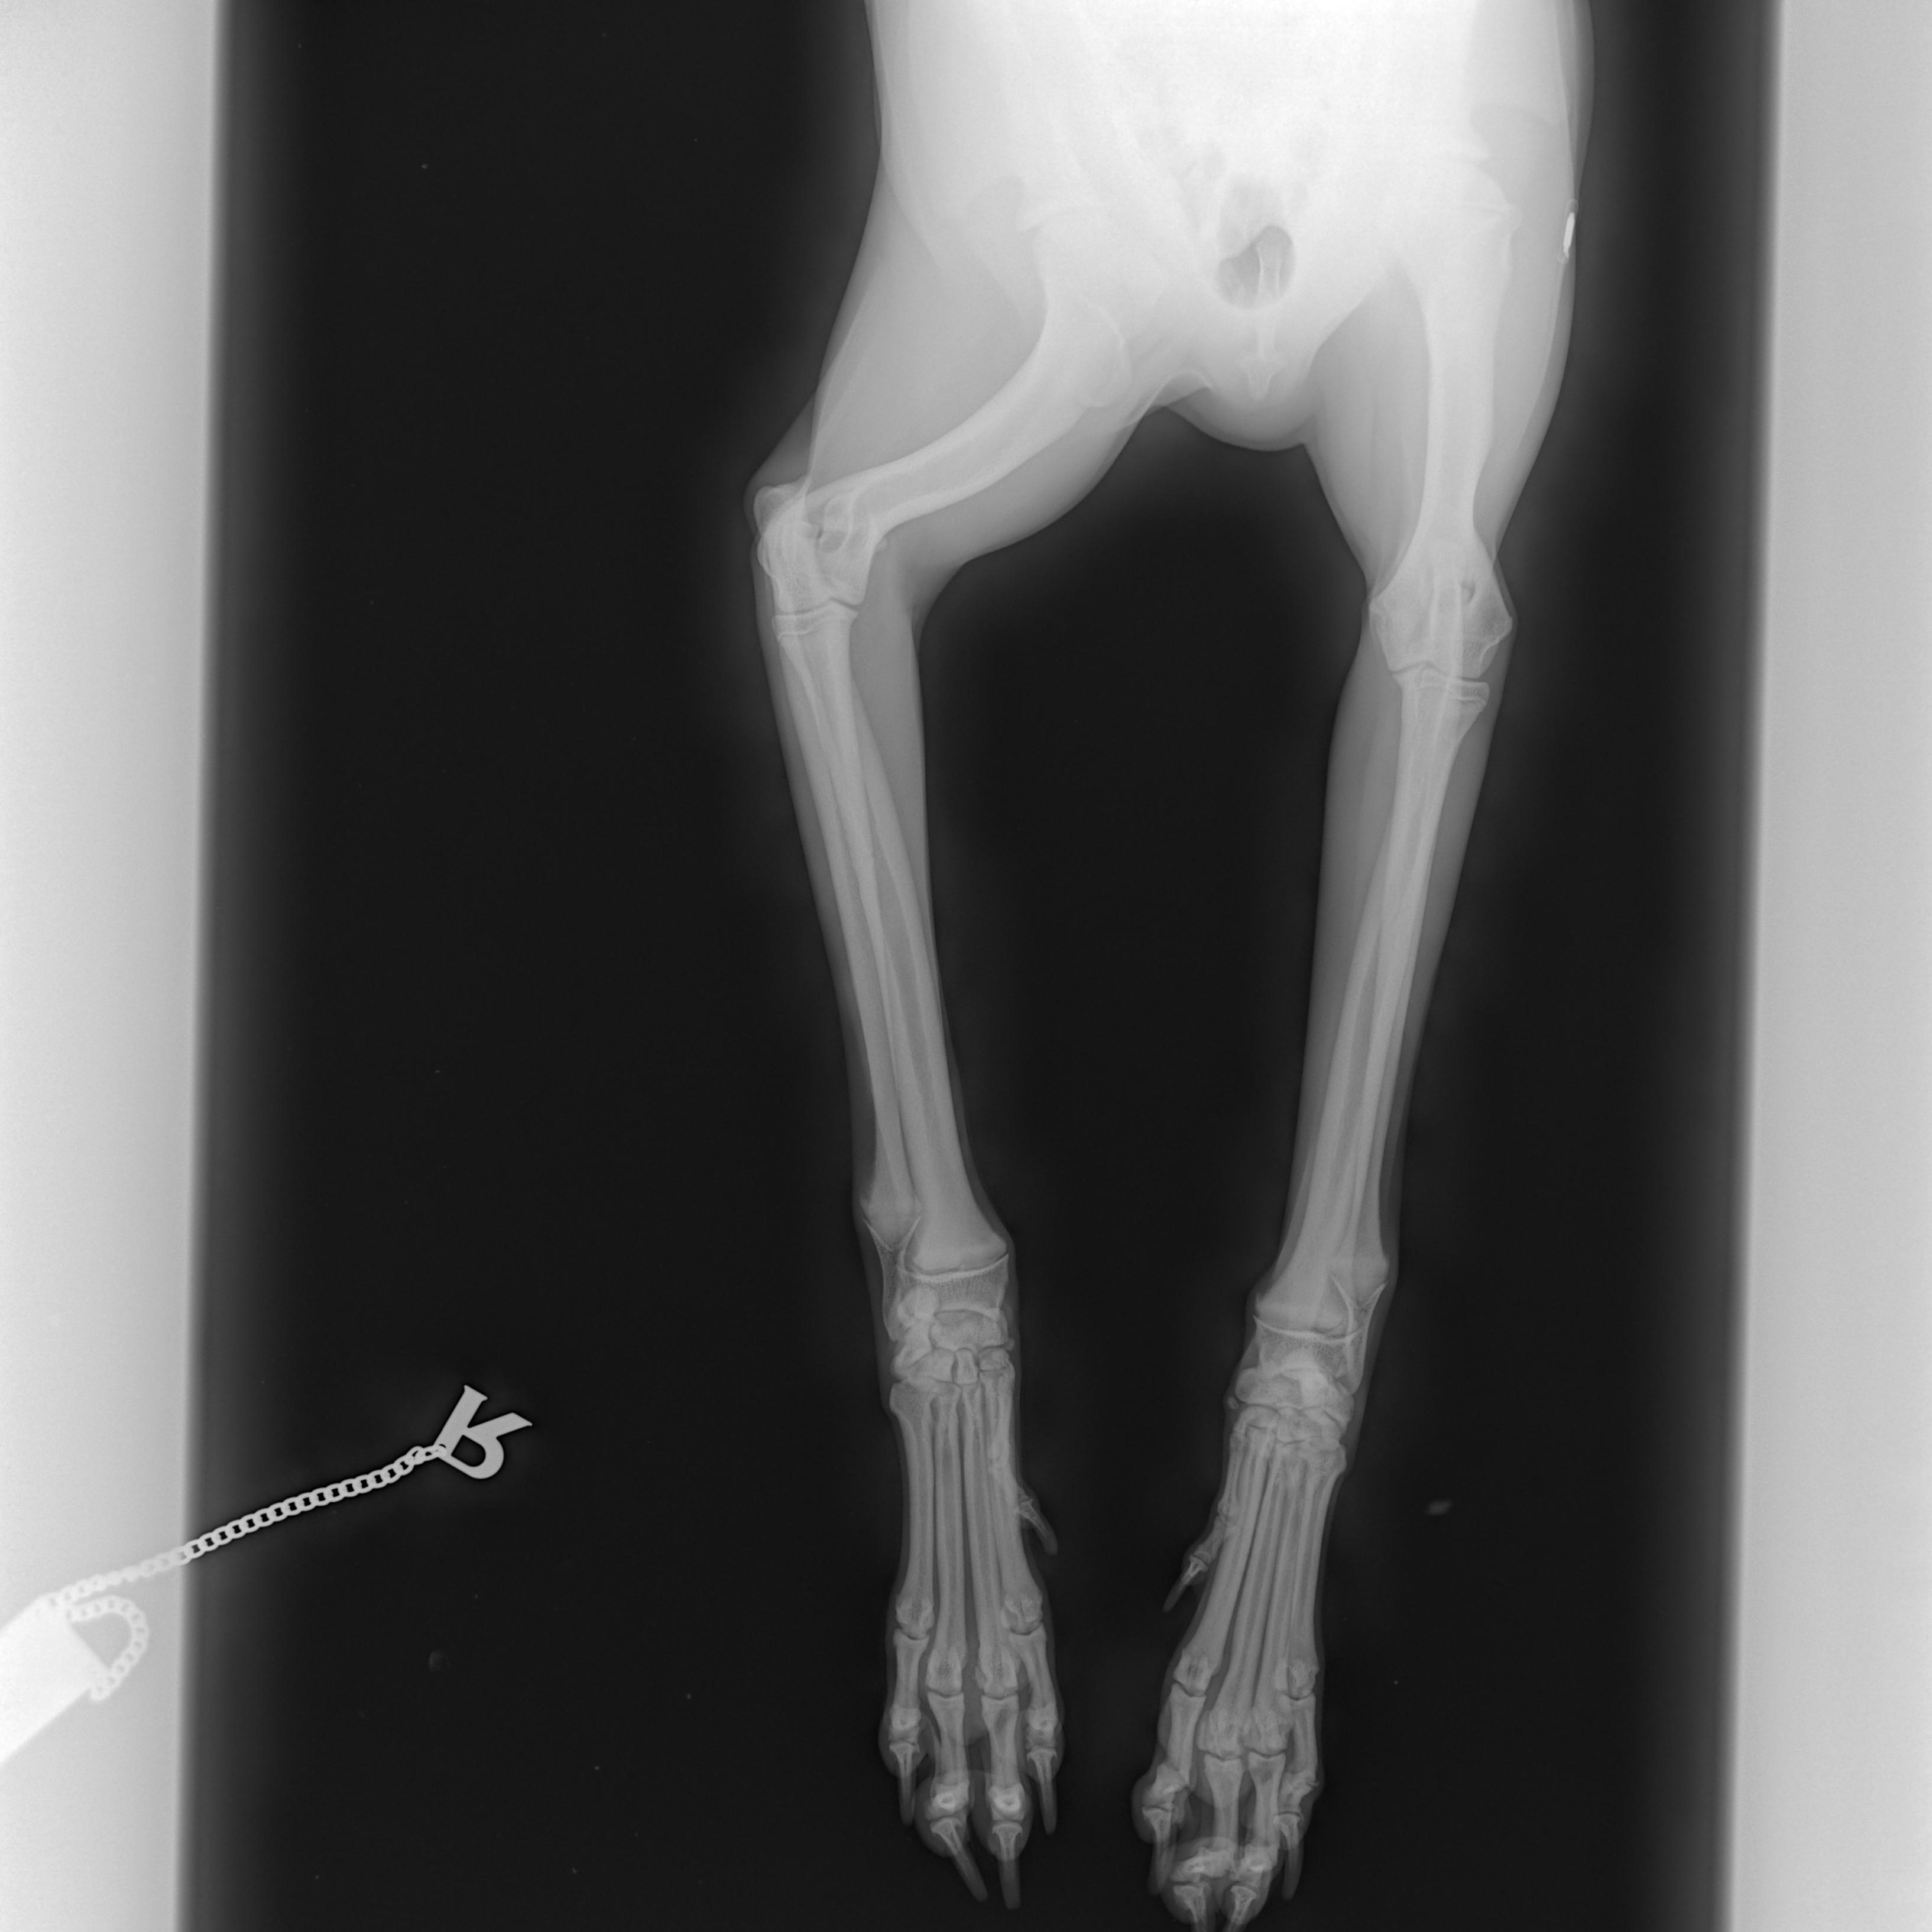

Cushingův syndrom, taktéž nazývaný Hyperadrenokorticismus, patří v současnosti spolu s diabetes mellitus mezi nejčastěji se vyskytující endokrinologická onemocnění psů. Způsobuje ho nadbytek glukokortikoidů, jako Cushingův syndrom pak označujeme soubor příznaků, které onemocnění doprovázejí.